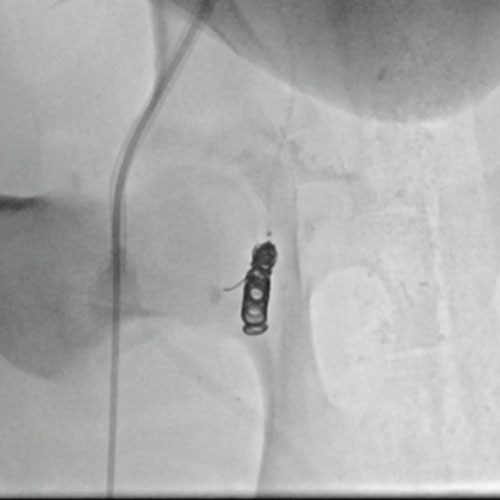

3 vs 2 Coils

Ruby Standard Coil shown  in right subclavian medial Ruby Standard Coil shown in right subclavian medial

Right Subclavian

Medial

3 Ruby Standard 6x20

Embold Fibered Coil shown  in left subclavian medial Embold Fibered Coil shown in left subclavian medial

Left Subclavian

2 Embold Fibered Coil 6x20